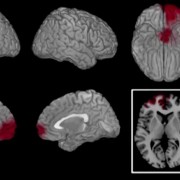

Il corpo come luogo della memoria traumatica

Le risposte traumatiche sono spesso implicite e non verbali: il corpo ricorda ciò che la mente non riesce ancora a raccontare.